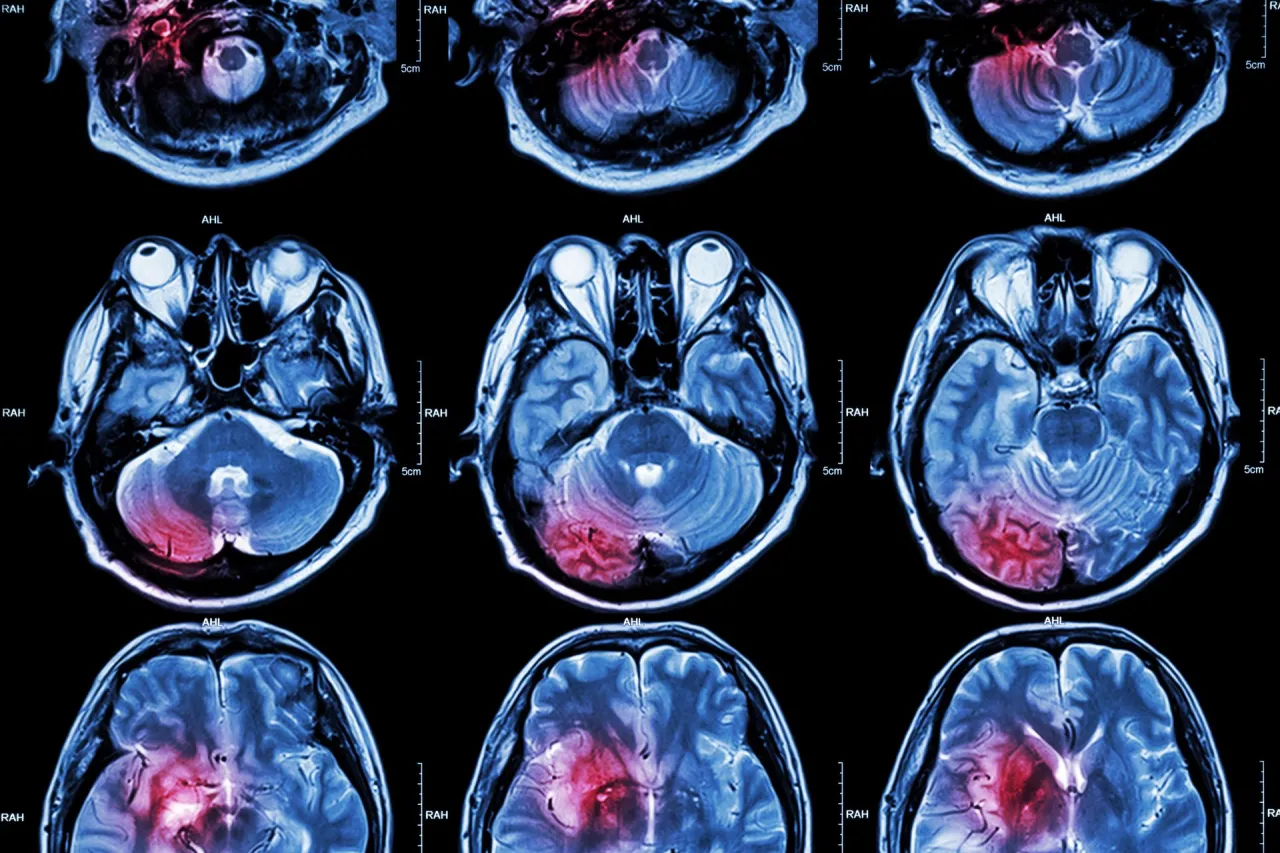

Udar niedokrwienny vs. krwotoczny: dlaczego rodzaj ma fundamentalne znaczenie? Około 80-87% wszystkich udarów to udary niedokrwienne. Powstają one, gdy skrzep krwi blokuje przepływ krwi do części mózgu, prowadząc do niedotlenienia i obumierania komórek. Rokowania w przypadku udarów niedokrwiennych są generalnie lepsze, zwłaszcza jeśli interwencja medyczna jest szybka. Z kolei udar krwotoczny, stanowiący mniejszość przypadków, jest znacznie groźniejszy. Polega on na pęknięciu naczynia krwionośnego w mózgu i wylewie krwi, co prowadzi do ucisku na tkanki mózgowe. Statystyki pokazują, że śmiertelność w przypadku udaru krwotocznego jest bardzo wysoka nawet połowa pacjentów umiera w ciągu pierwszych dwóch dni. Z mojej perspektywy, zrozumienie tej różnicy jest kluczowe dla oceny ryzyka i planowania terapii.Rozległość uszkodzeń w mózgu: im większy obszar, tym poważniejsze konsekwencje. To dość intuicyjne: im większy obszar mózgu został pozbawiony tlenu lub uszkodzony przez wylew krwi, tym poważniejsze będą skutki. Duże uszkodzenia mogą prowadzić do rozległych deficytów neurologicznych, takich jak paraliż, afazja (problemy z mową) czy głębokie zaburzenia świadomości, znacząco pogarszając rokowania zarówno pod kątem przeżycia, jak i odzyskania sprawności.

Czas to mózg: jak szybka reakcja medyczna ratuje życie i sprawność? To hasło jest fundamentem współczesnej neurologii udarowej. Każda minuta opóźnienia w udzieleniu pomocy medycznej po udarze niedokrwiennym prowadzi do obumierania milionów komórek nerwowych. Szybkie rozpoznanie objawów i natychmiastowe wezwanie pogotowia (numer 112 lub 999) jest absolutnie kluczowe. Im szybciej pacjent trafi do szpitala i otrzyma leczenie (np. trombolizę lub trombektomię), tym większe są szanse na ograniczenie uszkodzeń, a tym samym na lepsze rokowania i mniejszą niepełnosprawność. To jest aspekt, na który my, jako społeczeństwo, mamy realny wpływ poprzez edukację.